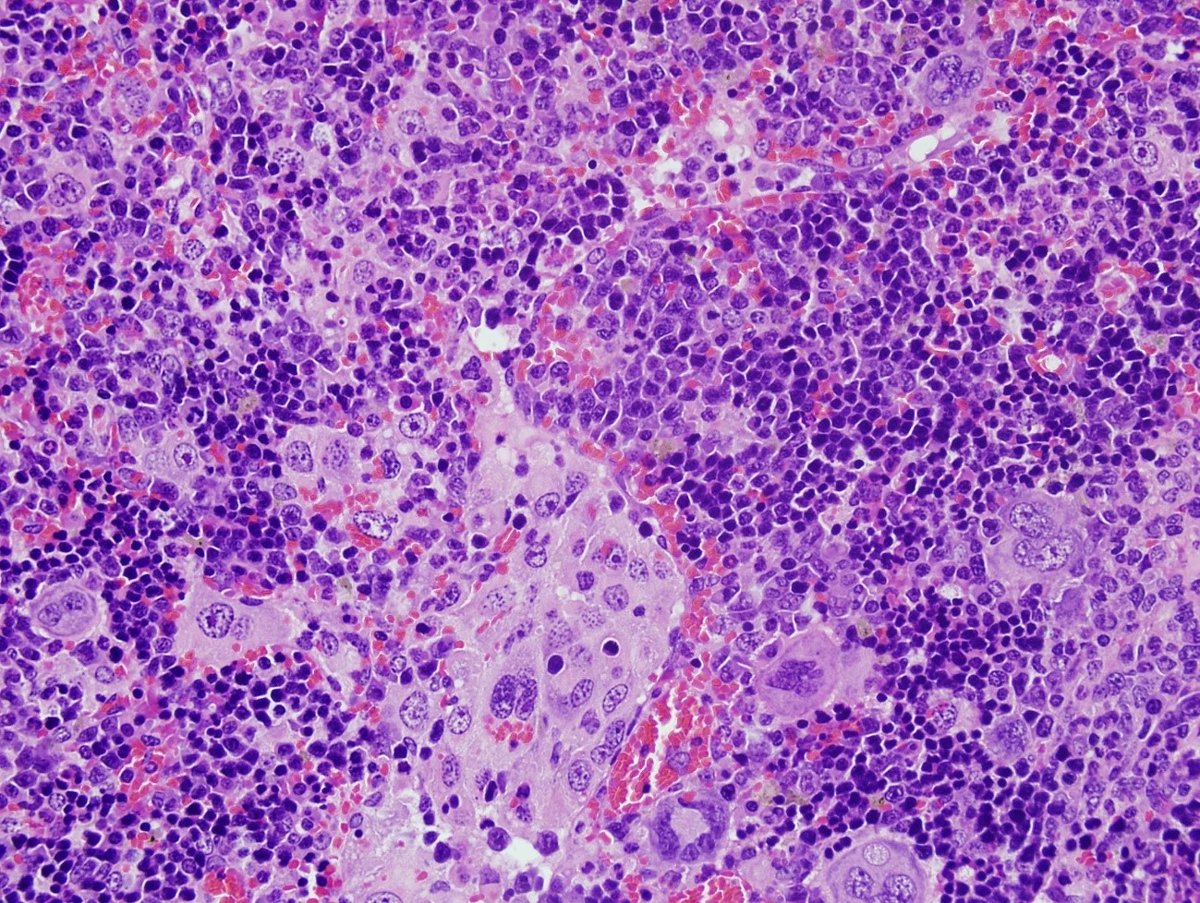

Archivo - Imagen de microscopia de un linfoma desarrollado por ratones con alteraciones en el gen VAV1.

Archivo - Imagen de microscopia de un linfoma desarrollado por ratones con alteraciones en el gen VAV1. - XOSÉ R. BUSTELO - Archivo